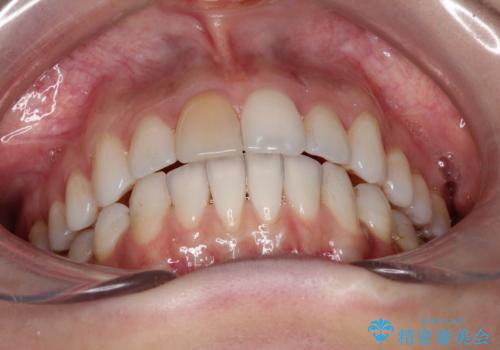

インビザラインによる非抜歯での八重歯の矯正

非常に強力的な患者様であったので、上下の正中も合わせ、ガタガタも改善することができました。